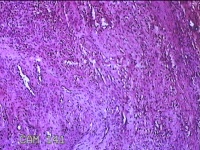

右侧食指远端结节

性别

男

年龄

47岁

临床诊断

皮下结节

一般病史

发现右侧食指3天。

标本名称

大体所见

灰白暗红色带皮肤样结节1.2x0.7x0.3cm一个,表面糜烂,切面灰白粉红色,质中。